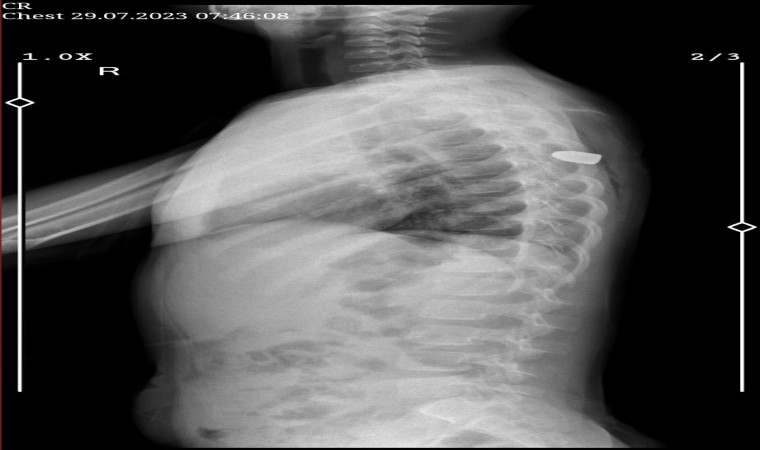

Edinilen bilgiye göre olay, merkez Seyhan ilçesi Aydınlar Mahallesi’nde geçen cuma günü meydana geldi. İddiaya göre, 6 yaşındaki Meliha Beray Ergün oturdukları sitenin bahçesinde oyun oynarken biranda yere yığıldı. Aile, kızlarının sesini duymaları üzerine hemen aşağı indi. Küçük kız, "Sırtımı herhalde böcek ısırdı, çok ağrıyor" dedi. Aile kızlarını Adana Şehir Eğitim ve Araştırma Hastanesi’ne götürdü. Burada çekilen ultrasonda Meliha’nın sırtına yorgun mermi isabet ettiği tespit edildi. Hemen ameliyata alınan ve hayati tehlikeyi atlatan Meliha’nın hastanede tedavisi sürüyor.

Kızının sağlık durumunun iyiye gittiğini söyleyen anne Ergün, “Şu anda tedavimiz devam ediyor ve kalıcı bir şey olmayacak inşallah. Çocuk daha bunun yorgun mermi olduğunu bilmiyor. Bize sırtının böcek ısırdığını söylüyor. Yetkili olmayan insanlar silah kullanmasınlar. Zevkleri için silah sıkmasınlar. Bir kutlama yaparken silah kullanmasınlar. Bunu istiyoruz. Ben hep haberlerde duyup üzülürdüm, şimdi bizim başımıza geldi” diye konuştu.